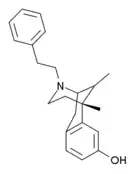

There are a number of broad classes of opioids:[260]

Benzomorphan derivatives

- Dezocine—agonist/antagonist

- Pentazocine—agonist/antagonist

- Phenazocine